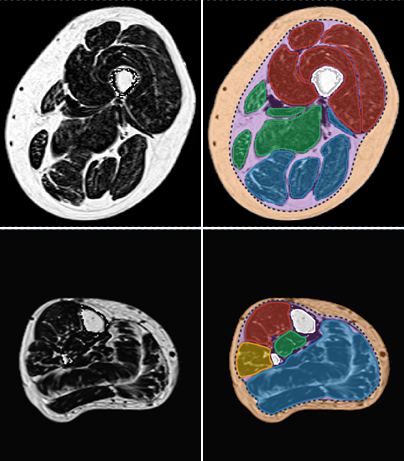

Examples of individual muscle segmentation on a medial axial section of a thigh (top) and leg (bottom).

Semi-automatic segmentation by propagation of the four individual muscles of the quadricep femoris on a 3D T1W sequence of the thigh.. Axial (left) and sagittal (right) views.